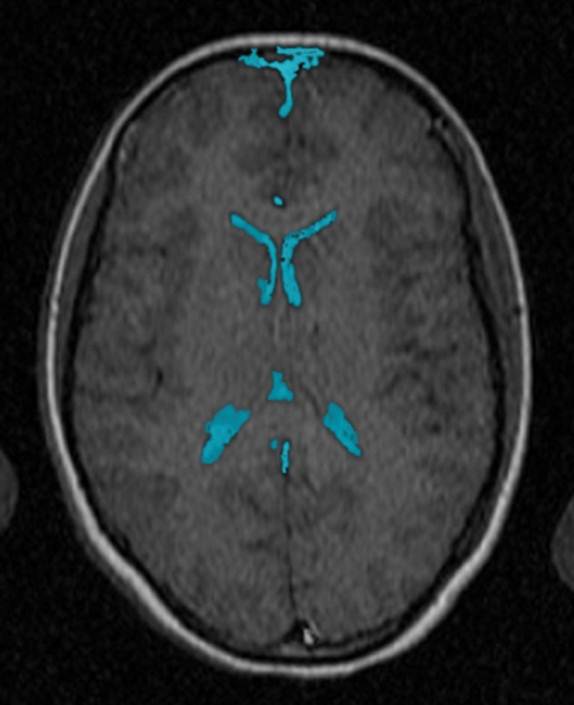

CT: Brain Atrophy